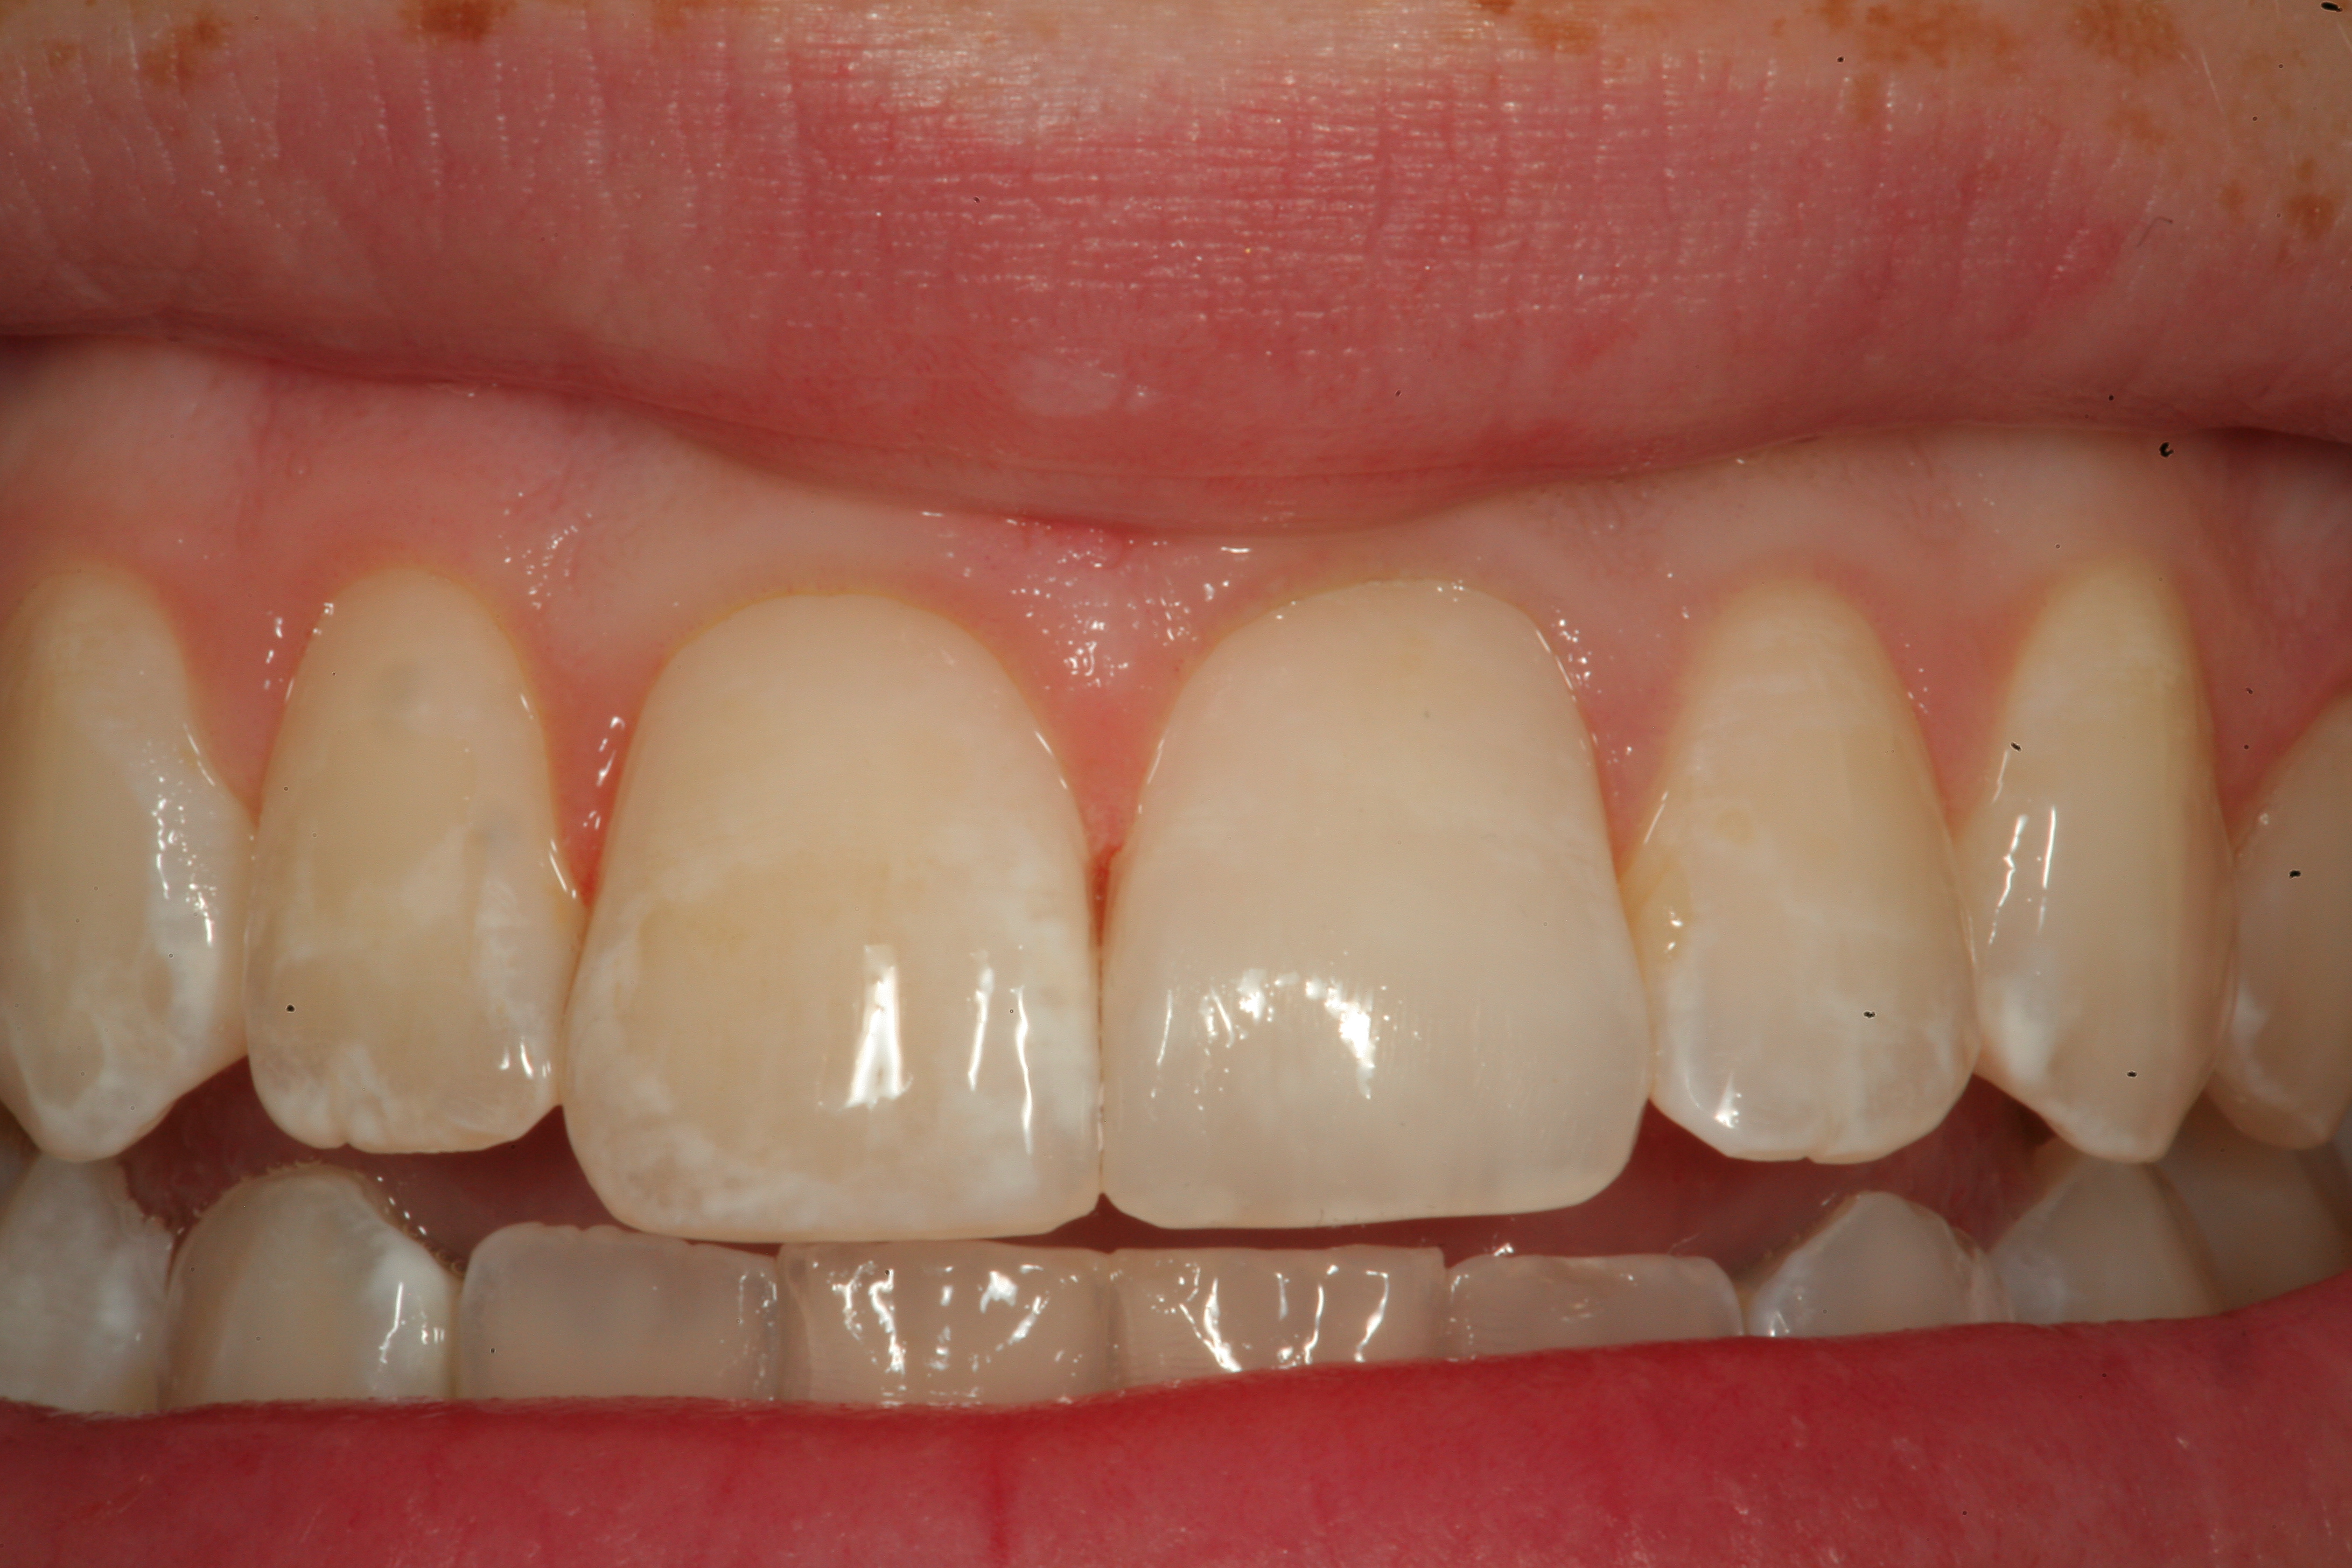

Fig 12. A Class IV mesial incisal fracture is shown from the facial aspect on tooth No. 9.

Figure 12